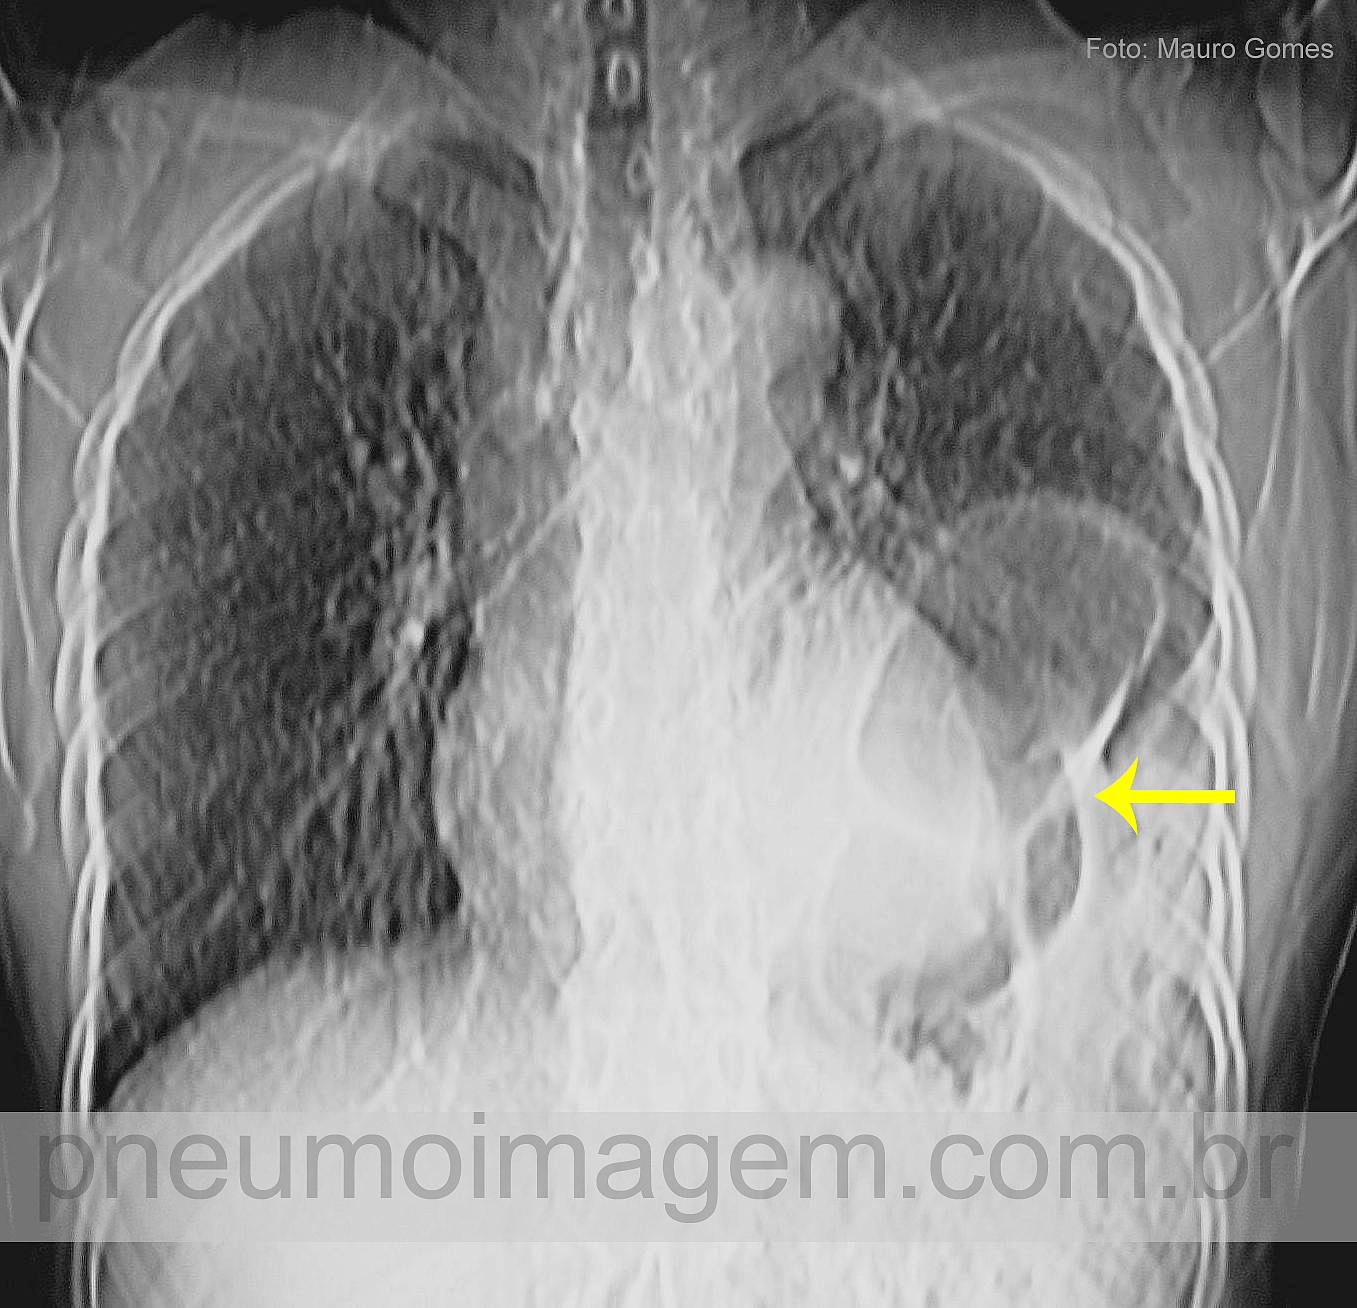

CASO CLÍNICO #42A imagem não está tão nítida pois foi extraída de um corte de tomografia, mas o caso é bem interessante. O que a seta aponta nesse corte? Deixe os seus comentários abaixo!

The image is not so clear because it was extracted from a CT scan, but the case is very interesting. What does the arrow point at this cut? Leave your comments below!

Parece-me hernia diafragmática traumática e herniação de cólon em sofrimento, pois está com paredes espessadas, reação pleural, etc.

Hérnia diafragmática com herniação de conteúdo do trato digestivo para o tórax.